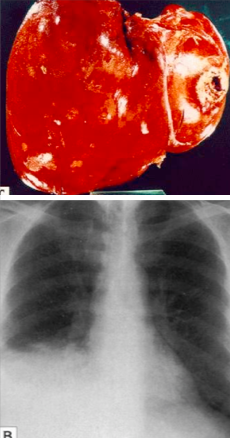

What syphilitic lesion is this?

Gumma. Type IV hypersensitivity causing fibrosis in many different areas of the body.